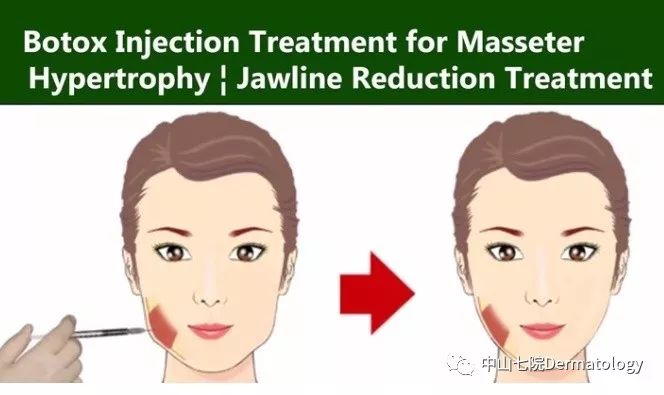

(2)轮廓塑性:以瘦脸为例,一部分人群脸大主要是因为咬肌肥大,肉毒素通过选择性萎缩部分肌肉从而让你瘦脸不是梦!!瘦腿瘦肩是一个道理,只是作用于不同的肌肉。

瘦脸